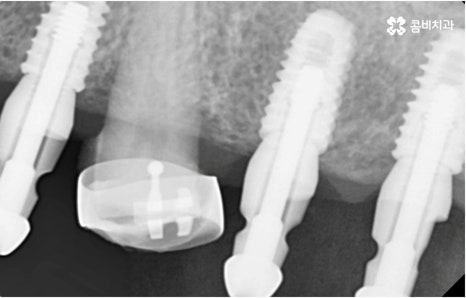

자연 치아를 살리기 위한 거의 마지막 단계의 보존 치료가 바로 신경치료, 재신경치료, 치근단절제술 등이며, 만약 치아재식술을 통해서도 살릴 수 없을 정도로 손상이 깊고 심하다면 해당 치아를 발치하고 임플란트를 통해 인공 치아로 대체해 줄 필요가 있습니다.

임플란트는 유치, 영구치 이후로 제 3의 치아라고 불리울 만큼 자연 치아의 상실에 대처하는 인공 치아 중에 가장 각광을 받고 있습니다. 저작력 회복이 80%에 가깝고 심미적으로 자신의 치아와 거의 다름없어 보이는 부분에서도 만족도가 높아 많은 분들이 찾고 있지만 식립 성공률과 안정적인 지속률에 크게 영향을 주는 올바른 위치 및 각도로의 식립을 무리하지 않게 진행하기 위해 술자의 높은 숙련도를 요하는 고난도의 수술이기 때문에 임상 경험이 많고 뛰어난 노하우를 갖추고 있는 담당의 선생님과 함께 하시는 것이 중요한 포인트라고 할 수 있어요.

환자분들의 상황에 따라 하루 만에 식립 및 임시 치아 장착까지 끝나서 바로 식사를 할 수 있는 원데이 임플란트 과정, 정밀 검사 후 디지털 장비를 이용하여 모의 수술 후 맞춤 가이드를 따라 무절개 / 최소절개 수술을 진행하는 네비게이션 임플란트 과정 등 관련 기술이 점점 더 섬세하게 발달하고 있어서 보다 편안한 이용이 가능하게 된 것은 사실이지만 본래 자신의 치아보다 좋은 인공 치아는 없을 것이기 때문에 건강할 때 이를 잘 유지 관리하고 구강 질환이 발생했을 때는 되도록 빠르게 이에 대처하실 필요가 있어요.